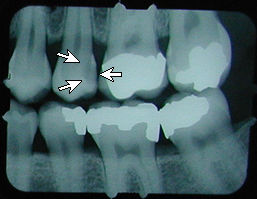

x-ray (previous)

No cavity on first x-ray.

Months later, cavities that start between the teeth can't be seen by visual examination, but they can be detected on an x-ray.